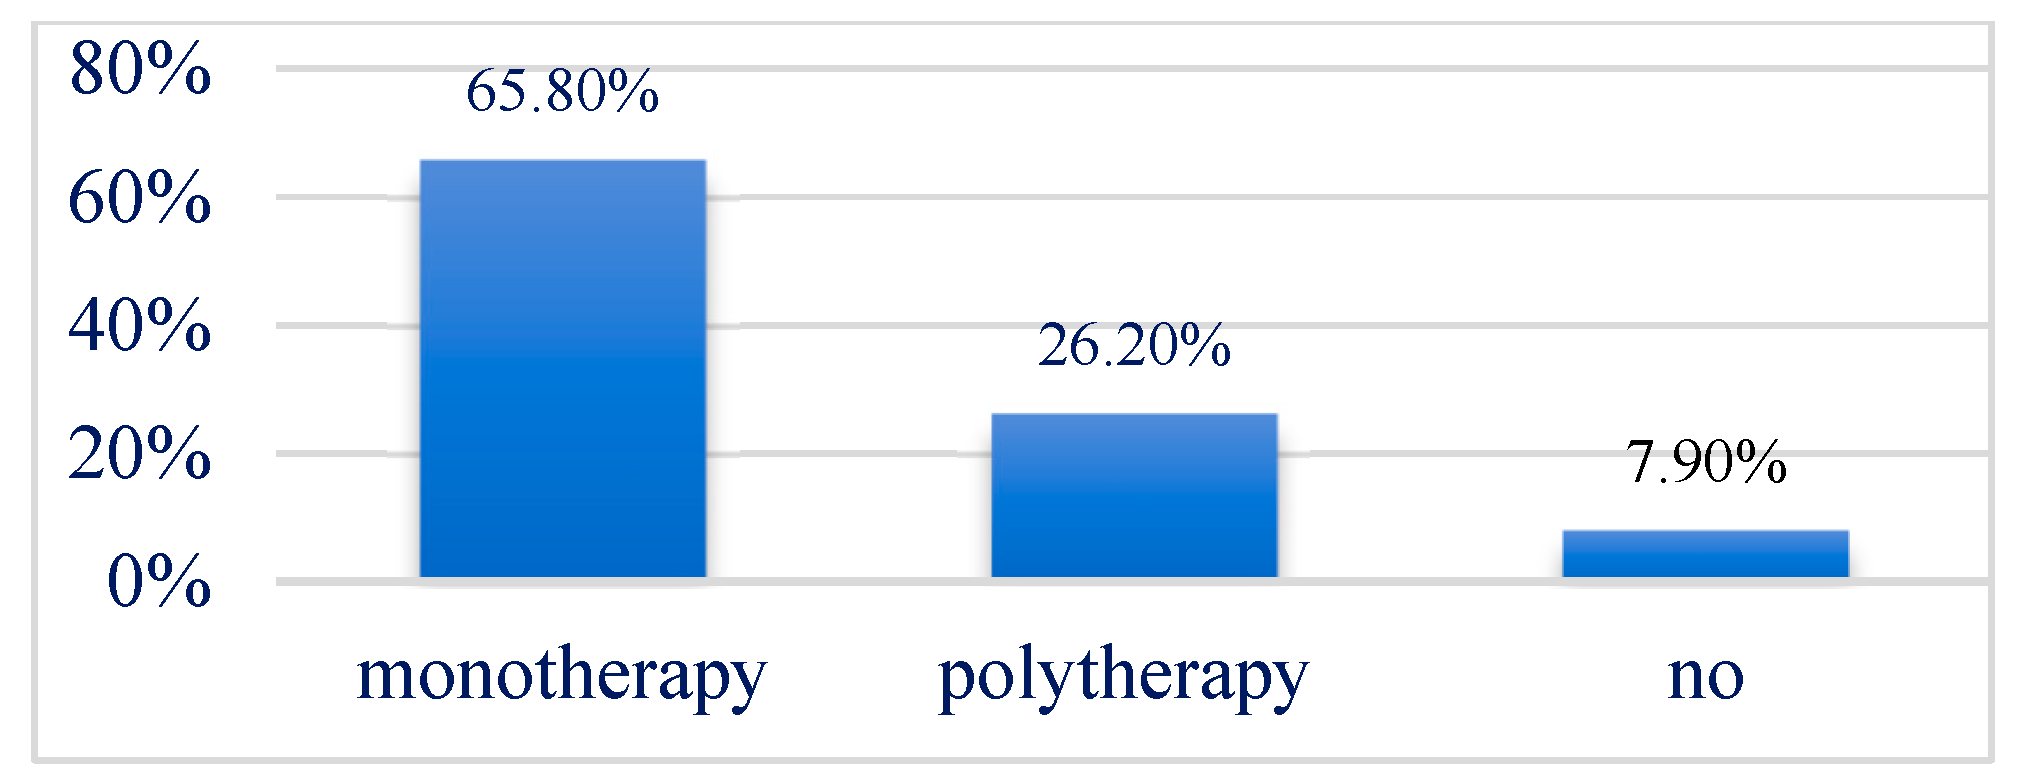

3.5. Treatment